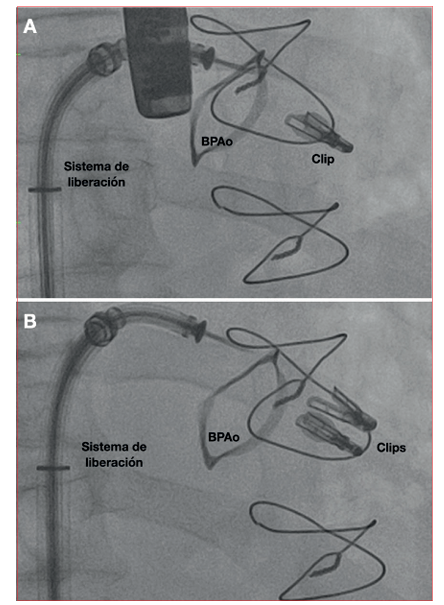

https://www.youtube.com/watch?v=gKopeZK-m2oSe discute el caso en heart team y por el elevado riesgo quirúrgico no se plantea cirugía convencional. Dada la factibilidad anatómica para realizar una reparación percutánea con técnica borde a borde, se opta por esta estrategia. El procedimiento se realiza bajo anestesia general, intubación orotraqueal y monitorización ecocardiográfica transesofágica continua. A través de un acceso venoso femoral derecho se realiza punción transeptal ecoguiada y mediante guía fluoroscópica y ecocardiográfica se implantan dos dispositivos MitraClip® (XTR y NT) a nivel de los festones A2-P2 de la válvula mitral (figuras 2 y3, video 2A). El ecocardiograma post implante (video 2 B y C) evidencia insuficiencia mitral remanente leve y gradiente transmitral no significativo (2 mmHg).

Figura 3 Fluoroscopía. A. Liberación del primer clip. B. Liberación del segundo clip. BPAo: anillo de bioprótesis aórtica.